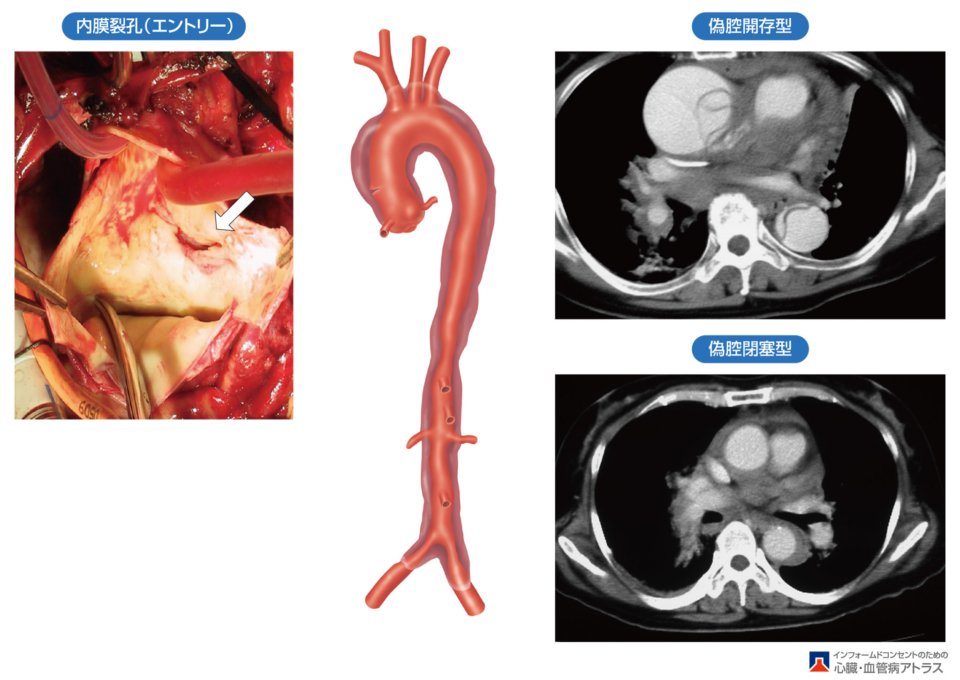

大動脈解離では、ときに他の病気とよく似た様々な症状がみられますが、通常はこの病気に特徴的な症状から明確に診断できます。. 大動脈解離がみられる人の一部では、腕と脚の脈が弱くなったり、感じられなくなったりします。. 大動脈に沿って起こった.. 1. 急性大動脈解離診断の基本方針. 急性大動脈解離(acute aortic dissection)は致死的疾患であり,的確に診断し,早急に治療方針を決定することが必要である。. 画像診断技術の進歩により,解離の形態を詳細に把握することが可能となった。. 解離の部位と.